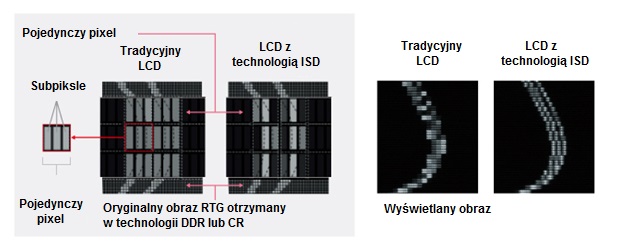

Funkcja niezależnego sterowania subpikselami - technologia ISD* (wyposażenie opcjonalne)

Ta unikalna technologia umożliwia monitorowi MS-S500 na renderowanie obrazów o rozdzielczości do 15 MsP, przekraczając tym samym obecne standardy podstawowej diagnostyki obrazów piersi. Monitor MS-S500 jest dopuszczony przez FDA 510 (k) do użytku w celach diagnostycznych z cyfrowymi obrazami mammograficznymi oraz obrazami tomosyntezy piersi.

| Przetwarzanie obrazu | Dostępne rozdzielczości | 2048 X 2560 pikseli,

ISD ON: 2048 X 7680 (2560 X 3 z wykorzystaniem subpikseli*)

* Do wyświetlenia na monitorze MS-S500 obrazów w technologii ISD z rozdzielczością 15MsP wymagane jest specjalne oprogramowanie. |

| Skala szarości / Kolory | 256 odcienie z palety 16369 odcieni szarości. *1024 odcieni szarości z wykorzystaniem złącza DisplayPort i przeglądarki obsługującej obrazy 10-bitowe) *Istnieje możliwość jednoczesnego wyświetlenia 1276 odcieni szarości (przy włączonym ISD) korzystając ze specjalnego oprogramowania. | |